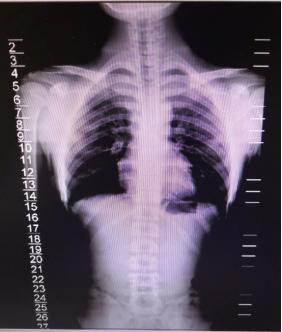

经X光检查发现,小胡的胸椎下段、腰椎轻度向右弯突,偏移角约3度。

幸运的是,小胡同学的脊柱侧弯幅度并不大,胥海斌主任医师团队采用“骨、筋、脉”三联疗法综合治疗几个疗程后,小胡的脊柱获得了完全的矫正。

小胡治疗前后X光检查对比